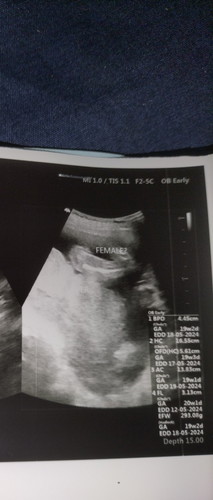

ลุงหมอบอกว่าน้องเป็นผู้หญิง แต่เราดูไม่เป็น ตรงไหนเพศน้องหรอคะ ซาวด์ตอน 20 วีคเต็ม #ขอบคุณสำหรับคำตอบค่ะ #ท้องแรกค่ะ

ในภาพอาจจะถ่ายออกมาไม่ชัดค่ะ แต่คุณหมอเขียนไว้ยุค่ะแม่ว่า FEMALE เพราะถ้ามีจู๋ 20w จะเห็นชัดแล้วค่ะ ของเรา 16 5 ชัดมาก จู๋ยื่นเลย

ภาพที่ถ่ายมาคือช่วงหว่างขาค่ะ ไม่มีกลมๆ แหลมๆออกมา เรียบแบบนี้ จิ๋มแน่นอนค่ะ